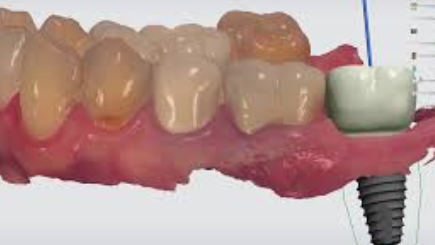

2단계 - 수술: 치과 의사는 어금니 부위에 구멍을 내고 임플란트를 천천히 삽입합니다. 그 후, 임플란트 주위의 뼈와 임플란트가 잘 결합되도록 치유를 위한 기간을 대기합니다. 이는 일반적으로 몇 주에서 몇 개월까지 걸릴 수 있습니다.

3단계 - 임시 크라운 설치: 치유 과정 후, 임플란트 주위의 뼈와 임플란트가 충분히 결합되었다고 판단되면 임시 크라운을 임플란트에 부착합니다. 이로써 환자는 일상적인 식사와 말하기를 할 수 있게 됩니다.

4단계 - 영구 크라운 설치: 뼈와 임플란트가 완전히 결합된 후, 임시 크라운을 제거하고 영구 크라운을 설치합니다. 이 과정에서는 어금니의 자연스러운 외관과 느낌을 제공하며, 장기적으로 안정성과 기능성을 보장합니다.